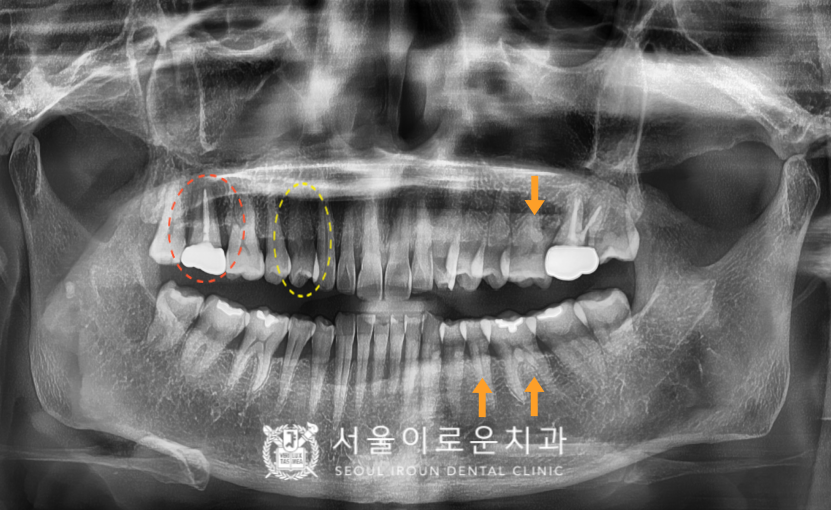

확인해 보았더니

노란색 동그라미 표시의

오른쪽 위 첫 번째 작은 어금니(#14)에서

불편감을 보이셨는데요.

x-ray 상으로는 크랙 라인이

또렷하게 관찰되지는 않지만

구내에서 확인하였을 때

상당히 깊게 크랙이

진행된 것으로 보였으며

타진 반응에도 통.증이 있었습니다.

안타깝게도 치아가 둘로 쪼개져

예후가 좋지 않아

발치를 해야 하는 상황이었답니다. (ㅠㅠ)

주황색 동그라미 표시의

오른쪽 위 두 번째 큰 어금니(#17)의

기존 보철하였던 치아가

동요도가 심하고, 뿌리까지 염증이

진행된 것을 확인할 수 있었습니다.

그리고 주황색 화살 표시의

왼쪽 위 첫 번째 큰 어금니(#26),

왼쪽 아래 두 번째 작은 어금니(#35)와

첫 번째 큰 어금니(#36)엔

치아와 잇몸 사이인

치경부 부위가 움푹 파여있는

치경부 마모증을 관찰할 수 있었는데요.